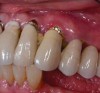

The keratinized tissue is measured from the gingival margin around the implant to the muco-gingival junction (Figure 8). Historically, an adequate zone of keratinized tissue was defined as 2 or more mm to maintain gingival health.20 Until now, the consensus remains divided on the importance of keratinized tissue surrounding implants. While some studies show implants with a greater amount of keratinized tissue had better plaque and gingival indices in addition to reduced alveolar bone loss surrounding the implant, opponents maintain there is no association between the lack of keratinized tissue and peri-implant bone loss despite greater plaque accumulation and gingival inflammation.17,21,22 Although the evidence is conflicting, readers are encouraged to keep in mind the different orientation of the gingival fibers around teeth and implants. Around natural teeth, the gingival fibers run perpendicular to the long axis attaching to the tooth surface, whereas around implants the fibers run parallel to the long axis of the implant and do not attach to the implant surface, providing a weaker mechanical barrier to plaque.

Figure 8. Peri-implantitis; note lack of keratinized gingiva surrounding implant.

Figure 8